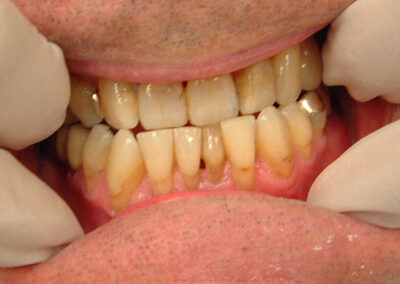

Da es keinen individuelleren Artikulator als das Kiefergelenk des betroffenen Patienten gibt, schleifen wir kleinere pathologische Befunde in der Regel gleich im Munde ein. In diesem Fall, in dem aufgrund der Schwere des Befundes nicht absehbar war, wie ausgeprägt und die Frontzahnästhetik verändernd die erforderlichen Maßnahmen sein würden, haben wir die Situation in einen halbindividuellen Artikulator übertragen. Es waren nur geringe subtraktive Maßnahmen im Frontzahnbereich erforderlich, um die Zwangsbisssituation aufzulösen. Auffälilg war, dass nachdem durch Entfernung einiger weniger konsekutiver Frühkontakte im linken Seitenzahnbereich befriedigende okklusale Verhältnisse hergestellt worden waren, eine ausgeprägte Nonokklusion im rechten Seitenzahnbereich persistierte.

Im linken Seitenzahnbereich mussten nur einige wenige konsekutive Frühkontakte entfernt werden, um funktionell befriedigende Okklusionsverhältnisse herzustellen.

Nach Einschleifen der progenen Zwangskontakte in der Front Nonokklusion im rechten Seitenzahnbereich

Nach Einschleifen der progenen Zwangskontakte in der Front und weniger konsekutiver Frühkontakte im linken Seitenzahnbereich funktionell befriedigende Okklusionsverhältnisse im linken Seitenzahnbereich

Das Einschleifen hat nicht nur die progene Zwangsführung beseitigt, sondern auch zu einer ästhetischen Harmonisierung der Front geführt.